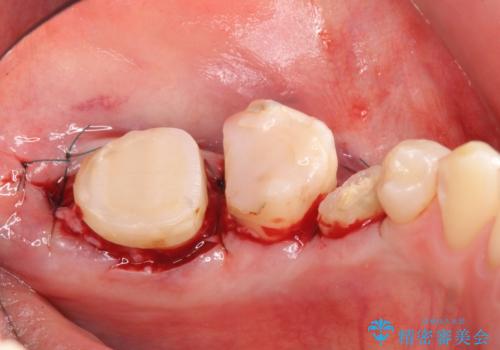

- 左下の奥歯がズキズキ痛むので診て欲しいといらっしゃった方の症例です。他院では5番目と7番目の歯を抜歯してインプラントと言われたが、出来れば歯を残したいとのことでした。

痛みの原因は6番目の虫歯であること、5番目、6番目の歯は歯茎より深い虫歯であり現状では保存が難しいことを説明した上で、歯を挺出させる部分矯正と歯茎を下げる歯周外科を行いました。

手術後歯茎の治癒を待ち、オールセラミッククラウンによる補綴を行いました。